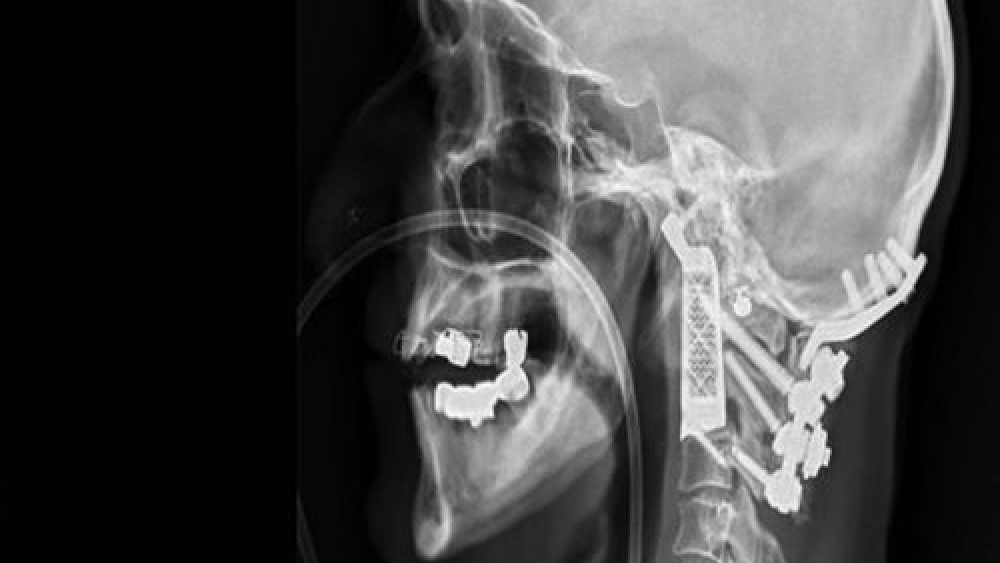

Avustralya, Sidney şehrindeki Prince of Wales hastanesinde görev alan beyin ve sinir cerrahı Ralph Mobbs, sağlık tarihine geçecek bir çalışmaya imza attı ve bir hastasının 2 omurgasını, 3D baskı teknolojisi ile hazırlanan omurga ile değiştirdi. 60 yaşlarında olan ve yakalandığı Kordoma adı verilen bir hastalığa sahip olan hastası için yapılan bu ameliyat olumlu sonuç verdi. Kordoma, omuriliğe baskı yapan ve sıkıştıran bir çeşit kanser hastalığı olarak tanımlanıyor.

Mobbs, Avustralya merkezli medikal cihaz üreticisi Anatomics ile bir çalışma yaptı ve titanyumdan hazırlanan birebir uyumlu 2 omurga hazırladılar. Bu gelişme ise tarihe bir ilk olarak geçti. Hazırlıkların ardından 15 saatlik ameliyat süreci başladı. Operasyon bölgesi ise beyin kökü, bazı ana damarlar ve omurilik bölgesinin hemen üstünde, yani son derece riskli ve dikkat edilmesi gereken bir bölgedeydi.  Ameliyatın en zor kısımlarından bir ise hastanın başını boyundan ayırıp, tümörlü bölgeyi temizleyip, başı tekrar boyuna yerleştirmekti. Mobbs ve ekibinin 15 saatlik operasyonu ise başarıyla sonuçlandı.